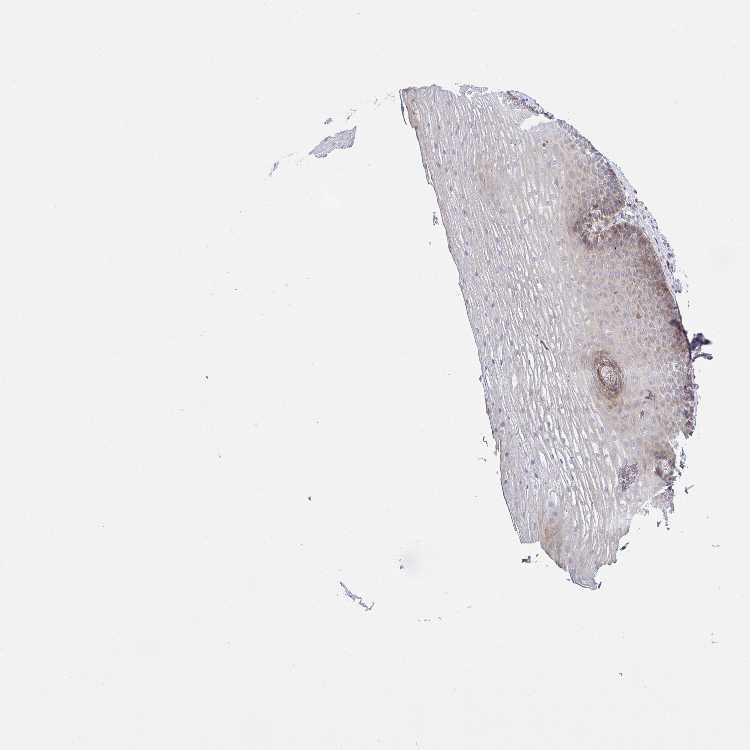

ESOPHAGUS - Antibody stainingi

Antibody staining in the annotated cell types in the current human tissue is reported as not detected, low, medium, or high, based on conventional immunohistochemistry profiling in selected tissues. This score is based on the combination of the staining intensity and fraction of stained cells.

Each image is clickable and will lead to virtual microscopy that enables deeper exploration of all samples and also displays staining intensity scores, fraction scores and subcellular localization as well as patient and tissue information for each sample.

Antibody HPA017285

Squamous epithelial cells Low